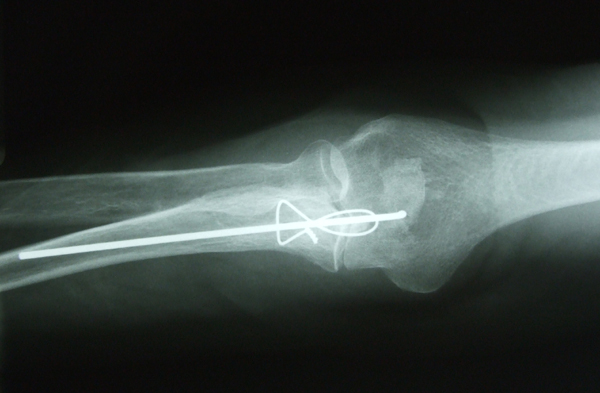

Fractura de olécranon con osteosíntesis.